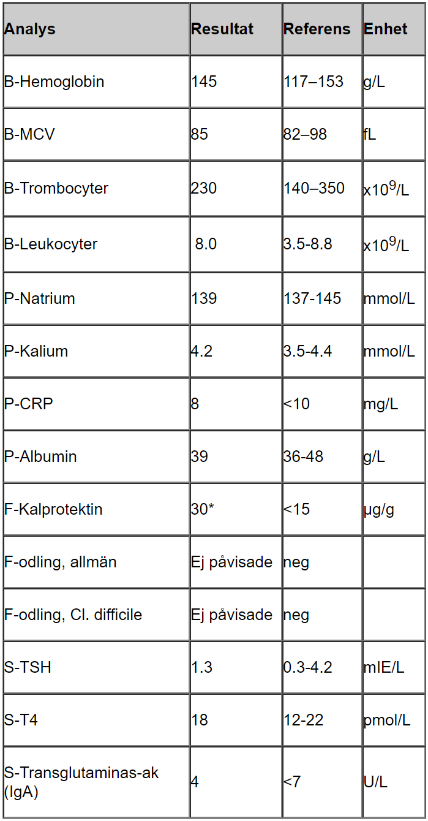

Tolka proverna

- B-hemoglobin, MCV, ferritin lågt vilket tyder på inflammation/blödning, eventuellt problem med näringsupptag

- Trombocyter högt som kompensation för blödning

- CRP lite högt tyder på låggradig inflammation

- Albumin lågt kan tyda på inflammation (omvänd markör)

- F-Kalprotektin högt tyder på IBD

- F-hemoglobin tyder på att det pågår blödning i tarmen, hon har inte uppmärksammat det själv vilket tyder på blödning något mer proximalt i tarmen